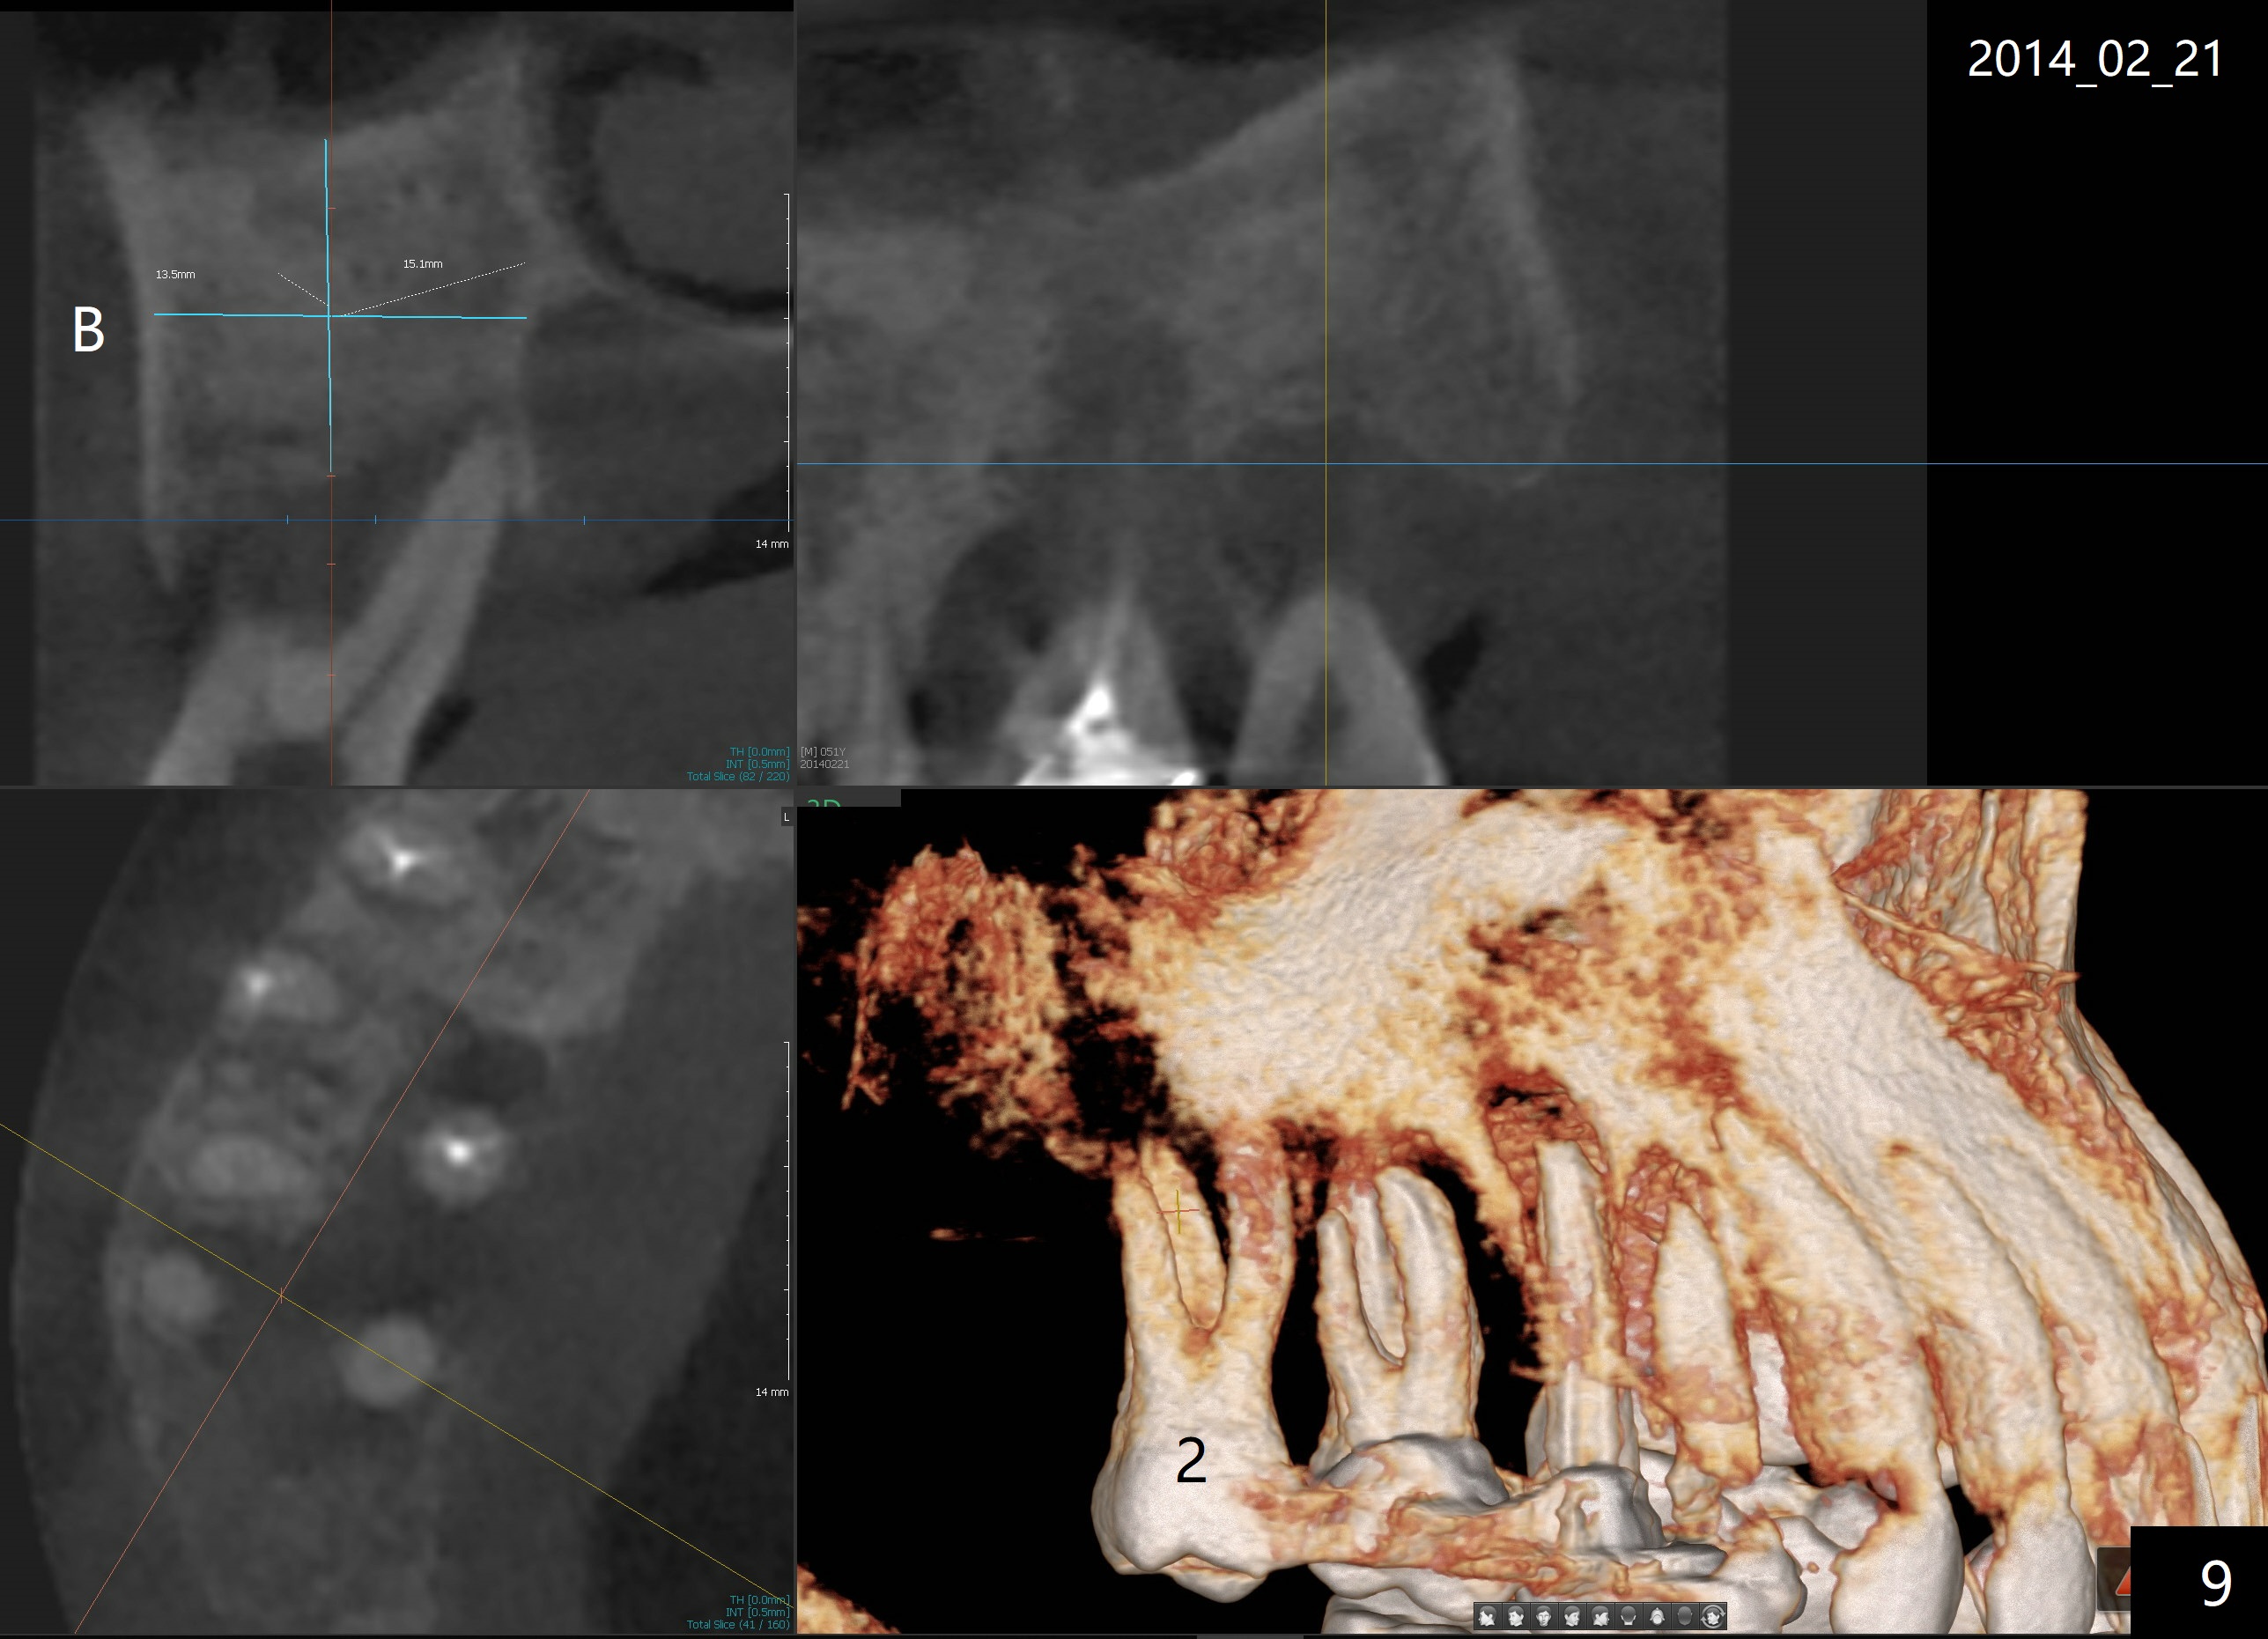

A 51-year-old man requests taking care of hemorrhage and odor associated with the tooth #3 (Fig.1). Due to religious and financial issues, the neighboring teeth will be treated later (supraeruption of #2 (arrow) and periapical radiolucency of #4 (*)). CBCT reveals that the septum of #3 is large enough to hold 4.5 mm implant (Fig.2). In fact osteotomy is created as planned in the septum using drills and taps (Fig.3 after removing 4.5x20 mm tap). Primary stability is obtained with a 4.5x20 mm implant (> 60 Ncm, Fig.4). The gap (*) is bone grafted; an abutment is placed (Fig.5 A); an immediate provisional is fabricated and cemented to cover the socket (Fig.6 P). When the socket heals in 3 weeks postop, the provisional and the abutment are removed for easy oral hygiene. Bone regenerates around the implant 3.5 months postop (Fig.7 *), but the 2nd molar has shifted mesially (arrow), presenting a restoration challenge.

It appears that the upper molar shifting is quite common (6 7), probably due to less dense bone in the maxilla. It is the best to fabricate and keep an immediate provisional to hold the mesiodistal dimension and ask the patient to improve local oral hygiene during osteointegration. The implant crown is functioning 4 years 2 months post cementation while there is severe bone loss at #2 (Fig.8). An immediate implant could be placed at #2 (Fig.9), while a wide delayed implant will be placed at #31 (Fig.10).